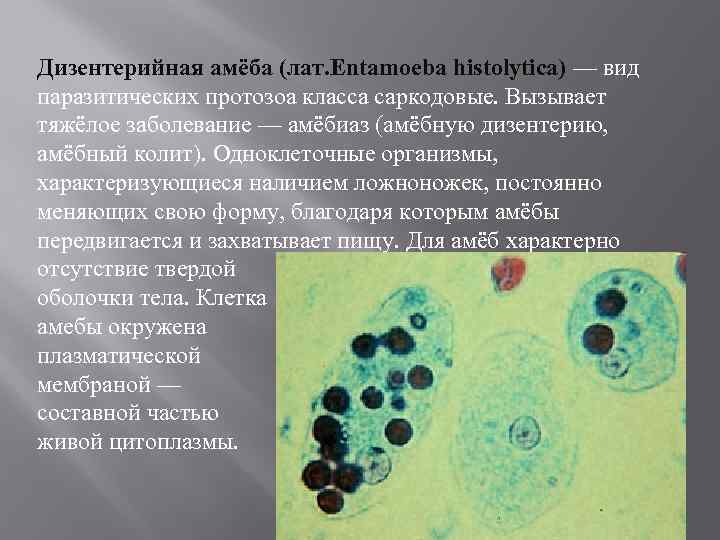

Структура клеток: Эктоплазма и цитоплазма в научных изображениях